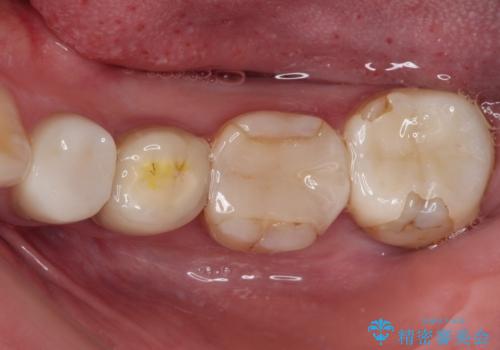

- 見た目の不揃いなセラミックと、痛みを感じる歯を気にして来院された患者様です。

右上の歯は噛んだときに何カ所か痛みを感じるとのことで、診査したところ第二小臼歯が患歯と疑われました。

患者様は他の歯にも痛みを感じるとおっしゃっていましたが、そのような所見が認められなかったため、まずは第二小臼歯を処置し、その痛みが引いた後に再診査することとしました。